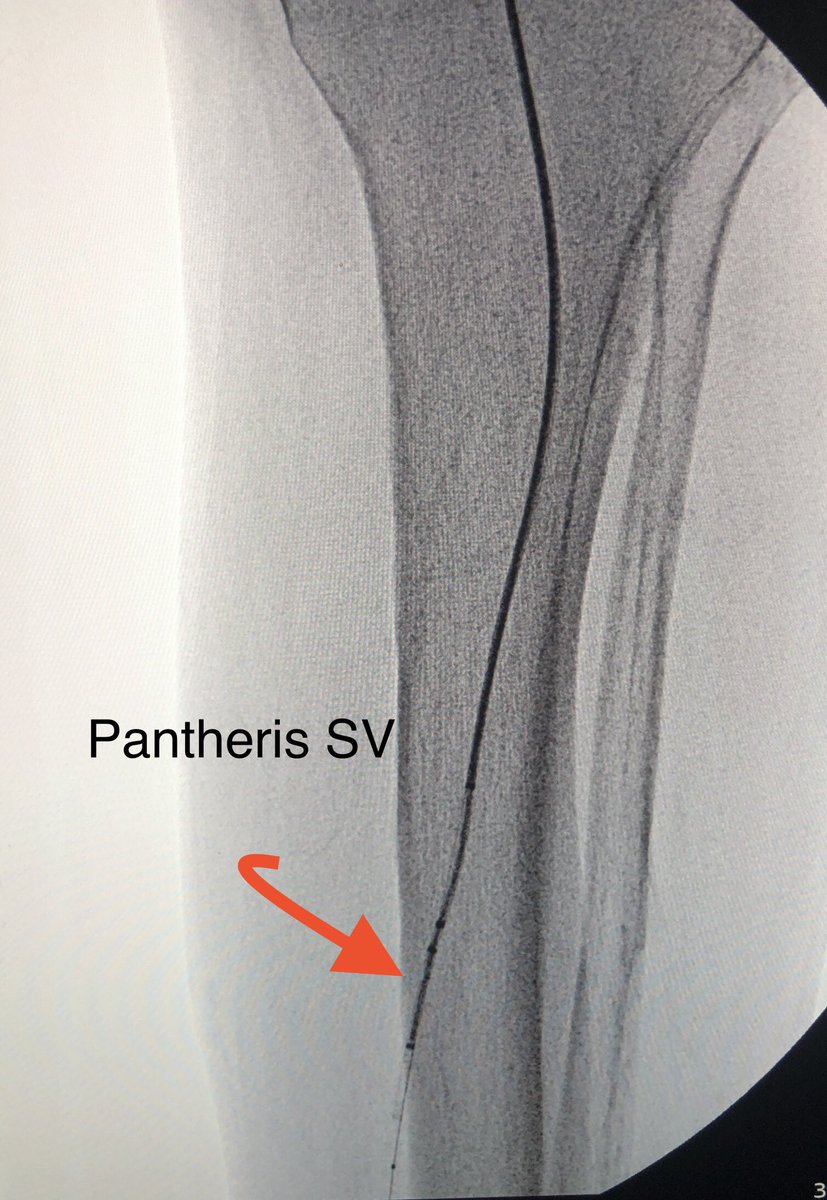

First look at Tigereye ..... 1000 rpm in single direction, deflectable tip, exchangeable support cath. I used the deflecting tip to precisely re-entry true lumen. Alot to learn to harness the power of #tigereye but gr8 start @AvingerInc